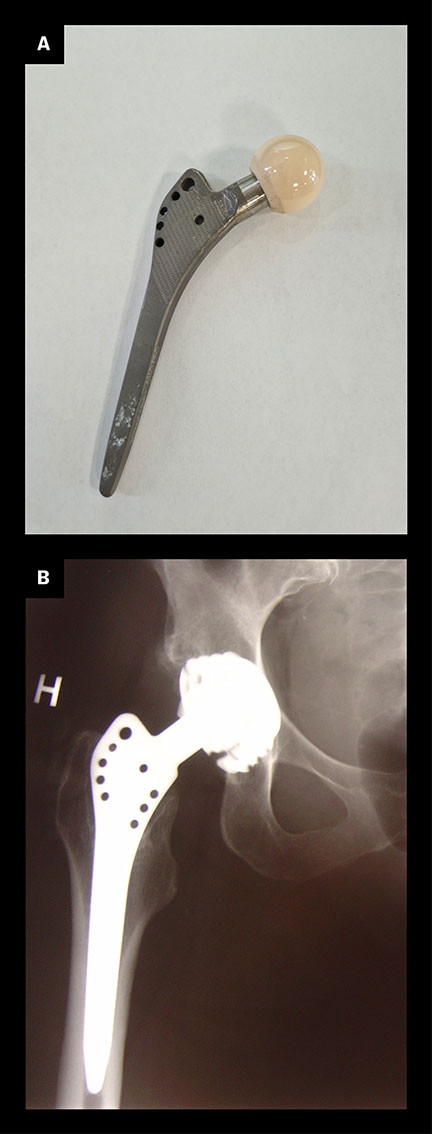

Interessen for ortopedisk bruk av titan kom noe senere enn i tannmedisinen, men tidlig på 1980-tallet ble det klart at sementfrie hofteproteser med en legering av kobolt, krom og molybden (CoCrMo), i medisinen kjent som Vitallium, ga dårlig feste til bein og svake kliniske resultater (13). Problemene førte til en økt interesse for forbedring av usementerte proteser. En større forståelse av hvordan implantater integreres i bein, førte til utviklingen av den første sementfrie titanprotesen for hofteleddet. Den ble tatt i bruk under navnet Zweymüller, etter wienerortopeden som startet utprøvingen av den i 1980 (14) (figur 2). I Norge ble femurproteser av titan tatt i bruk i 1984 (15). Alle usementerte primære femurproteser som nå settes inn i Norge, er av titan, og 20-års overlevelse for disse protesene er vist å være på over 90 % (16).

Titans aktive overflate gjør at metallet ikke egner seg for bruk som glideflate i ledd. For leddkulen i hofteleddet benyttes heller en legering av kobolt, krom og molybden, stål eller keramikk. Ved brudd i lange rørknokler er kirurgisk stål mest aktuelt. Plater, skruer og margnagler av titan brukes derimot ved osteosynteser i mindre knokler. Hos amputerte kan margnagler av titan som stikker ut gjennom huden, koples til eksterne proteser, på lignende måte som ved tannimplantater. Dette kan for eksempel gi protesefunksjon hos pasienter med korte amputasjonsstumper i femur eller humerus, hvor det ellers er vanskelig å feste eksterne proteser. Pasienter med et slikt protesekonsept får en slags «osseopersepsjon» via den osseointegrerte margnaglen som gir en mer korrekt følelse av hvordan protesen beveger seg og hvordan underlaget er. Sårdannelser og infeksjonsfare i overgangen mellom hud og margnagle kan opptre, men er ikke et stort problem (17).